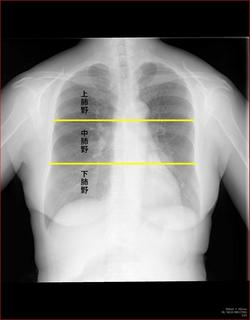

陰影があったときに、果たしてその陰影はどこにあるのか。

上、中、下肺野のどこにあるかとともに、シルエット・サインをうまく使うことでどのセグメント(

1〜10に分かれている、例のやつ)を絞り込むことができます。